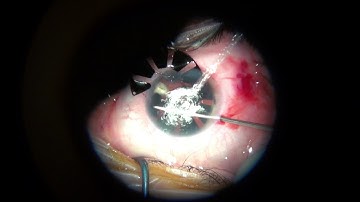

Morcher 96F partial aniridia segment for post-IFIS iris transillumination